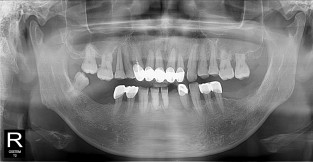

• 2

전체어금니

치료기간 : 2021-11-08 ~ 2022-12-22

1. 상기 x-ray 이미지 모두 동일한 해당 의료기관에서 진료한 환자입니다.

2. 상기 x-ray 이미지 모두 동일 인물의 것입니다.

3. 치료 전 이미지는 2021-11-08에 촬영했으며, 치료 후 이미지는 2022-12-22에 촬영하였습니다.

4. 상기 x-ray 이미지 모두 동일 조건에서 환자분의 동의를 받아촬영되었습니다.

* 임플란트 시술은 환자분의 상태(고혈압, 당뇨 등)에 따라 부작용이 있을 수 있으니, 반드시 전문의와 상담이 필요합니다.

* 임플란트 수술 부작용

: 수술 후 출혈, 교합, 통증, 붓기, 염증 등의 문제점이 발생할 수 있습니다.)

* 본 이미지들은 의료광고법을 준수하여 게시하였으며, <의료법 제 56조 제2항 제7호>에 의거하여 개개인의 신체 상태와 질병 진행도 등 여러 요인에 따라 치료 효과가 상이하기에 진료계획 또한 달라질 수 있음을 고지해드립니다.